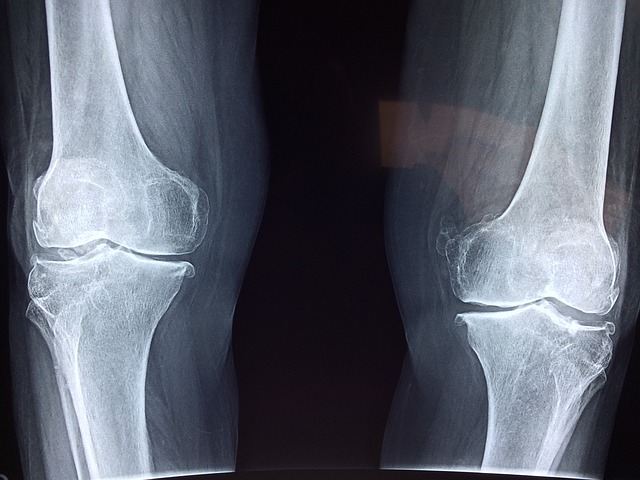

- 뼈와 관절에 영향을 미치는 문제. 여기에는 부러진 뼈(골절) , 관절 탈구, 감염 및 관절염이 포함될 수 있습니다.